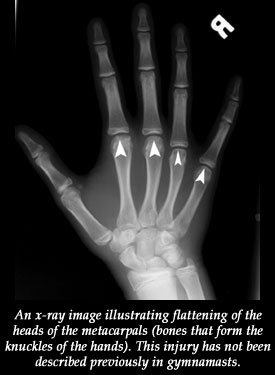

In their study, Dwek and his colleagues found that while growth plate injuries predominate in younger children who have the fastest growing bones, after children turn 13, the pattern of chronic injuries may not be limited to gymnast's wrist. Other injuries are also common, including some to the elbows, wrist, and knuckles that have not been described in the literature in association with gymnastics.

These sorts of injuries are probably due to chronic repetitive trauma, says Dwek. They include abnormal bone growth or abnormal bone loss. There were girls in the study who had unusual inflammation in their hands. Their MRIs also showed a flattening of the knuckles and knuckle "necrosis," or tissue death.